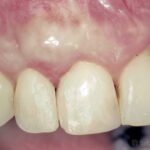

Para casos com boa qualidade de mucosa queratinizada, um envelope vestibular recebe a porção desepitelizada do enxerto pediculado.